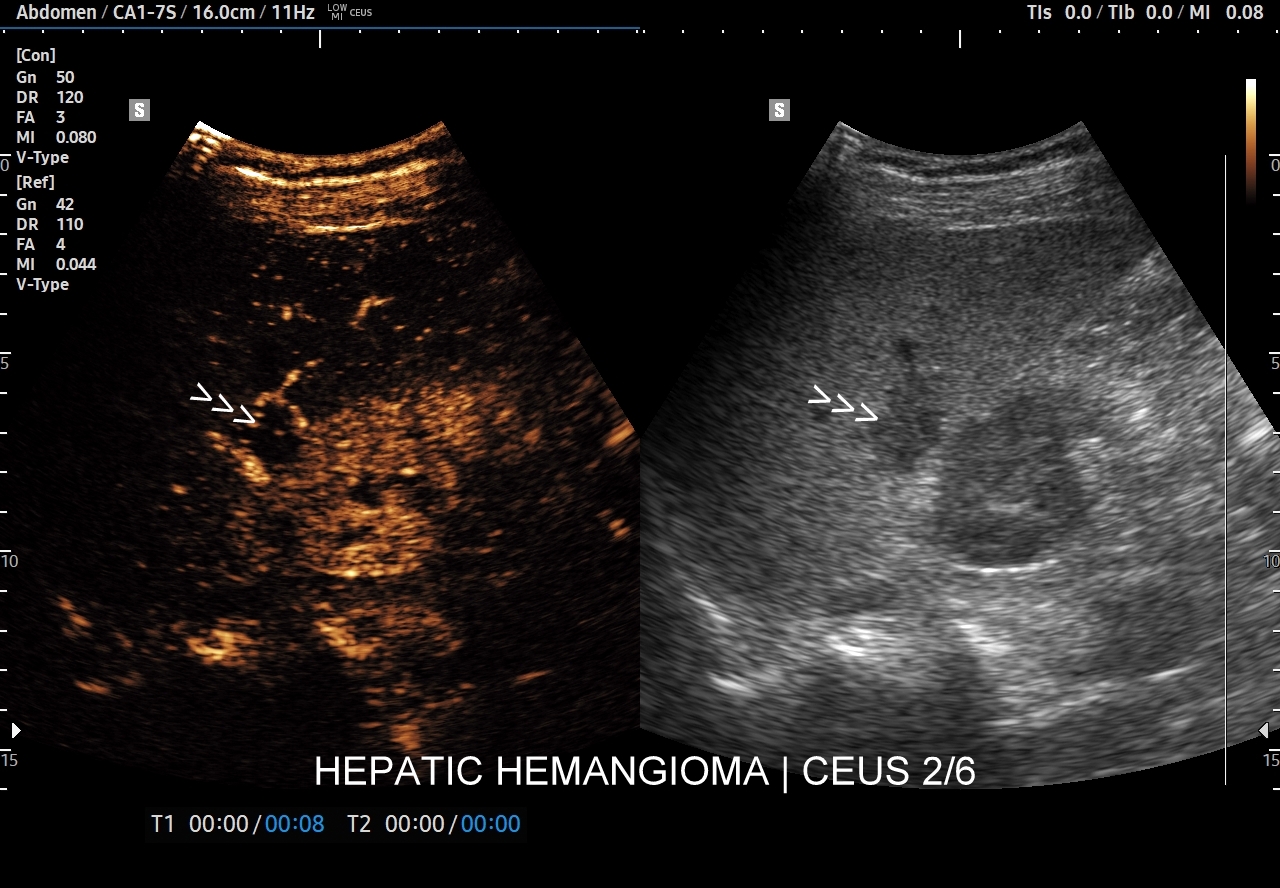

Najbardziej charakterystyczną cechą naczyniaka wątroby w badaniu CEUS jest jego wypełnianie w postaci guzkowej (ang. peripheral nodular enhancement) od obwodu ku centrum zmiany (ang. centripetal). Szybkość wypełniania bywa różnorodna, może być powolna lub szybka. W przypadku szybkiego wypełniania (tzw. flash-filling), w celu wykazania charakterystycznego centrypetalnego wypełniania niezbędna może być postprocessing’owa analiza poklatkowa zapisanego nagrania badania. W fazie późnej naczyniak wątroby pozostaje izowzmocniony lub hyperwzmocniony w stosunku do natywnego miąższu wątroby.

W przypadku dużych naczyniaków obszary, które uległy wykrzepianiu pozostają awaskularne przez wszystkie fazy badania CEUS, tj. nie wypełniają się kontrastem (nonenhancing). W przeciwieństwie do powyższego konstelacja, w której to w fazie wczesnej pojawia się wzmocnienie, a następnie w fazie wrotnej lub późnej ulega wypłukaniu (hypoenhancement) świadczy o cechach złośliwych diagnozowanej zmiany ogniskowej w wątrobie i wyklucza rozpoznanie naczyniaka.